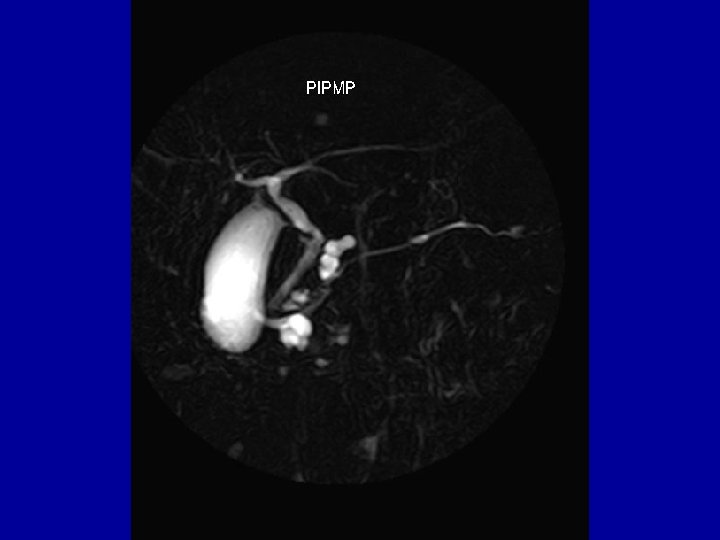

Imagerie par Résonance magnétique